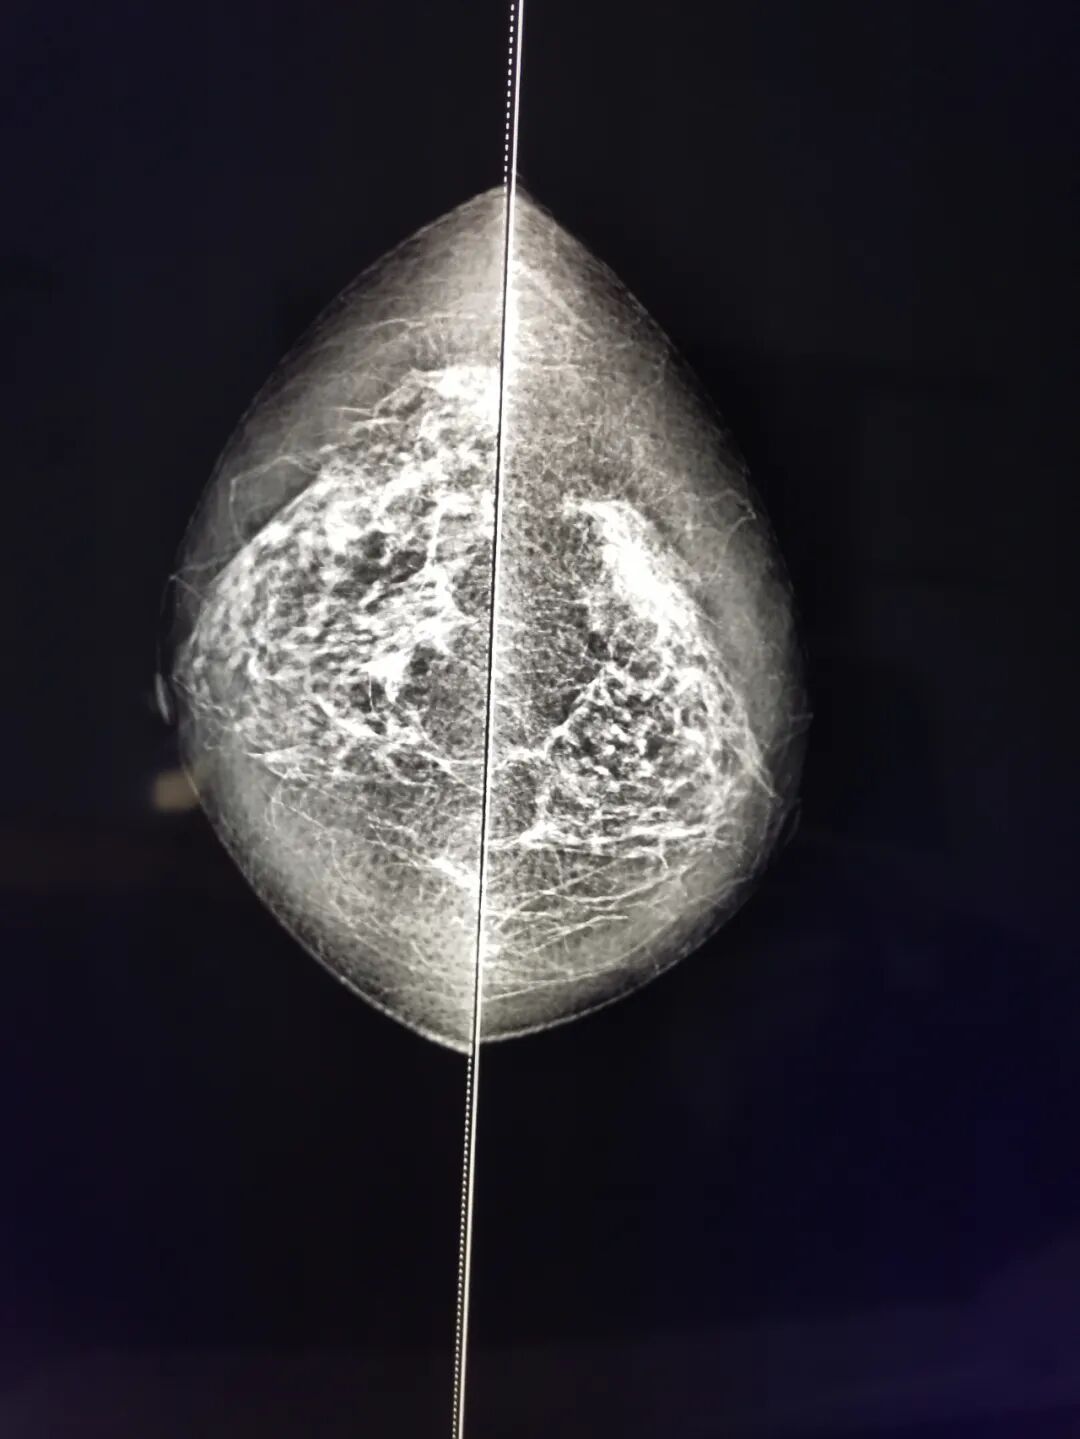

(乳腺钼靶X线机)

在我国的女性恶性肿瘤发病率中,乳腺癌居于首位,发病率在万分之五十以上,并呈年轻化及逐年上升趋势,同时,乳腺癌也是我国死亡率上升速度最快的恶性肿瘤。定期体检、及早发现、正确诊断、有效治疗是防止乳腺癌发生、发展的重要手段。我院每年针对农村适龄妇女开展的免费两癌(宫颈癌、乳腺癌)筛查,正是加大对“两癌”早诊早治率的措施。同时我院妇女群体保健科也专业针对女性检查制定了系列套餐。

乳腺钼靶有什么优点?

乳腺钼靶对于彩超和核磁无法鉴别的钙化病变可以进行准确辨别,且安全、辐射低、分辨率高、成像清晰、灵敏度低、结果精准,我院放射科最新引进的万东数字化乳腺钼靶X线机,可清楚显示乳房内小于1 cm的结节性病灶。而对于以少许微小钙化为唯一表现的T0期乳腺癌(临床门诊阴性),也只有凭借软X线检查才能被早期发现和诊断,其对乳腺癌的诊断敏感性为82%~89%,特异性为87%~94%,并可准确定性、定位。乳腺钼靶摄影能检查出“隐匿性乳腺癌”和早早期的原位癌,其辐射剂量亦降低至每人次(两侧四位)0.003Gy以下,对人体无损害。

乳腺钼靶检查试用哪些人群?

1、四十岁以上妇女的健康体检;

2、乳腺肿块、硬化,异常的乳头溢液,皮肤异常,局部疼痛或肿胀;

3、筛查发现的异常改变;

4、良性发现的短期随诊;

5、乳腺移植的患者;

6、乳腺肿瘤治疗的患者;

7、其它需要放射科医师检查或会诊的患者。

乳腺钼靶x线摄影是目前诊断乳腺疾病的首选最简便、最可靠的检查手段,具有全面直观、操作简单、无创安全和费用低廉等特点,已成为公认的乳腺癌临床常规检查和乳腺癌预防普查的最好方法之一。